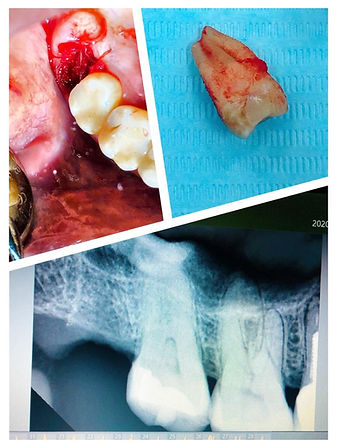

Удаление зуба мудрости(8ка).

Как правильно удалять зубы мудрости ( "восьмёрки") , которые полны неожиданных сюрпризов?? Конечно поручать необходимо опытному, высококлассному специалисту. Нужно потратить пару минут на ознакомление с отзывами той или иной клиники, стоматолога, хирурга, чем потом потратить не один месяц разбираясь с последствиями халатных действий. Испугались? Не стоит. К счастью, профессионалов в клинике Invitadent достаточно. Удаление " восьмёрки" под крылом нашего опытного врача Медведевой Анастасии состоялось на Ура!!!

Это частный случай указан на фото.

Наша команда готова Вам помочь с этой проблемой.